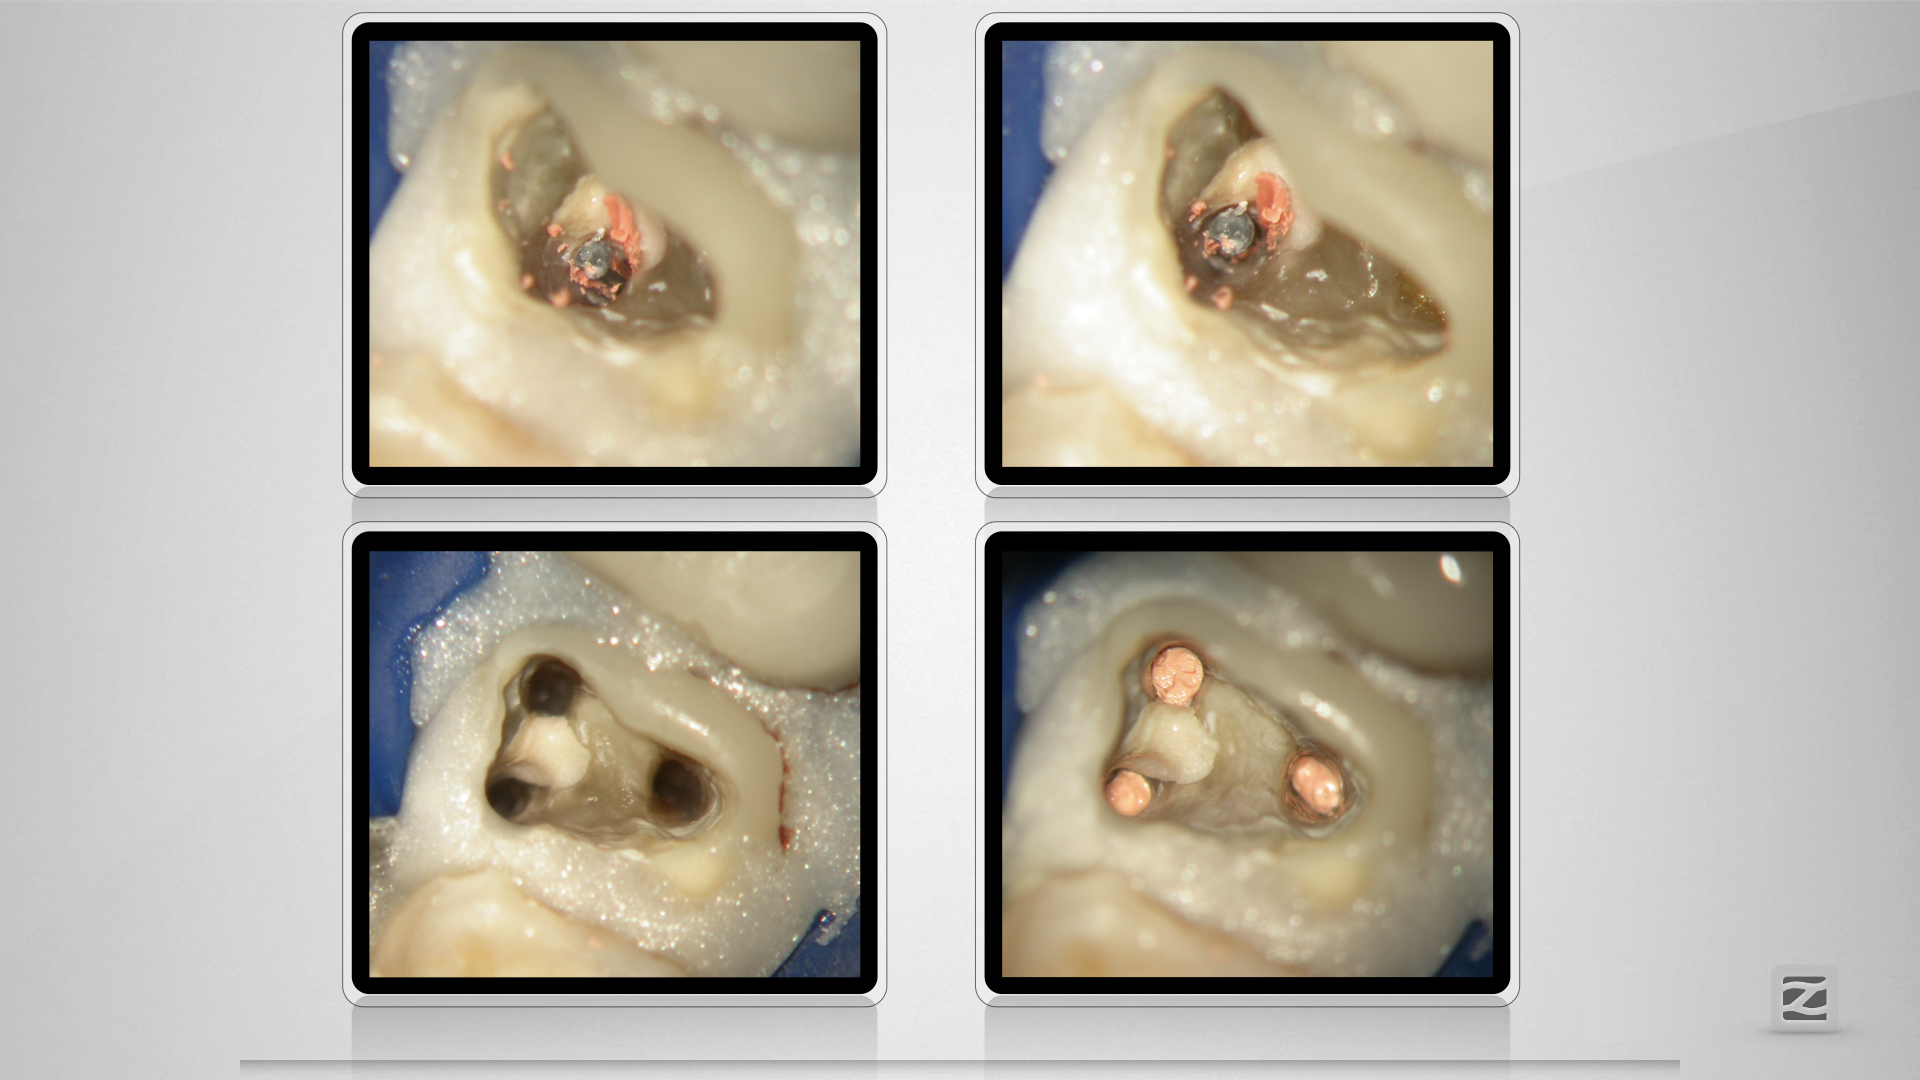

27D.011

Fast getroffen ist auch vorbei!